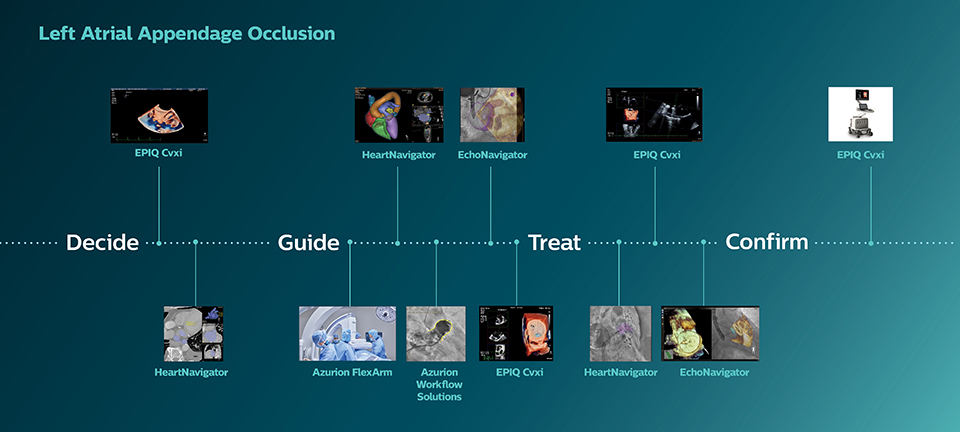

Soluciones clínicas para el tratamiento de cardiopatías estructurales

Explore varios procedimientos de terapia guiada por imágenes para las cardiopatías estructurales